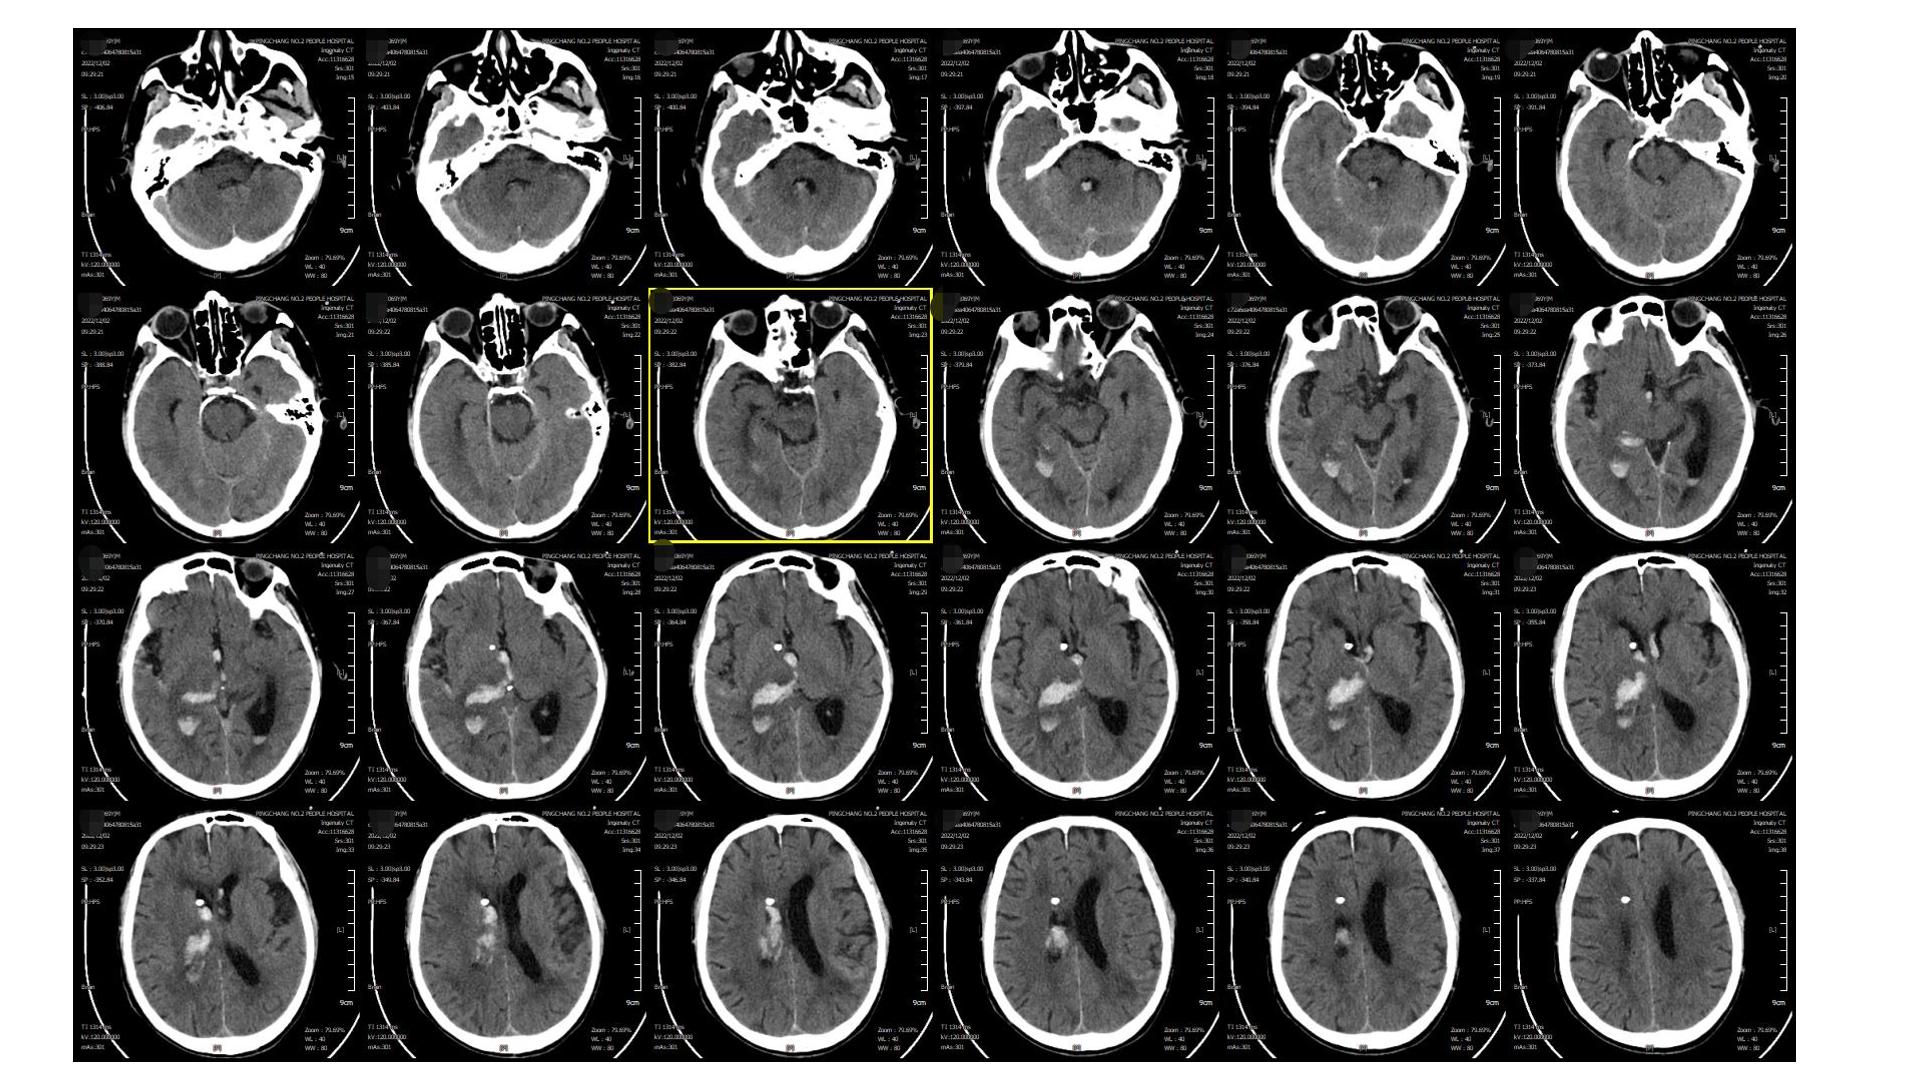

2022.12.02复查(EVD术后),无新增异常,予以局部使用尿激酶

2022.12.03

2022.12.07

2022.12.12

2022.12.12,血肿基本干净,留取脑脊液送检无颅内感染征象,予以拔除EVD引流管,腰穿释放蛛网膜下腔血性脑脊液